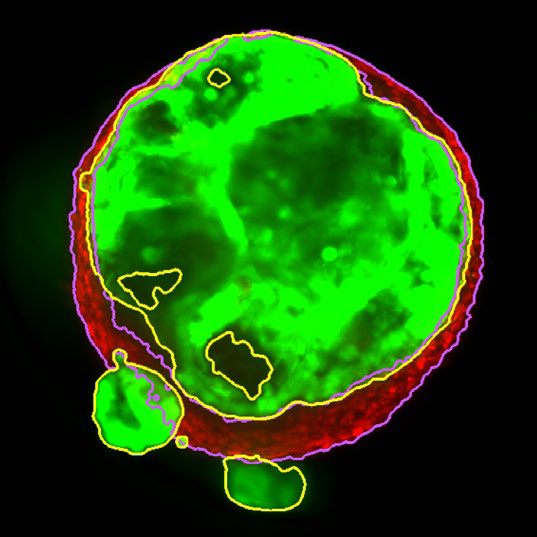

MaxIP image of 3D tumor co-culture microtissue - NCI-N87-GFP (gastric carcinoma; green) and NIH-RFP (murine fibroblast; red)

Figure 2. MaxIP image of 3D tumor co-culture microtissue - NCI-N87-GFP (gastric carcinoma; green) and NIH-RFP (murine fibroblast; red). Image Credit: Yokogawa Life Science

Tumor spheroids were created by seeding an Akura 384 plate with a monodispersed mixture of GFP-expressing NCI-N87 (gastric carcinoma) and RFP-expressing NIH3T3-L1 (murine fibroblast) cells, which spontaneously formed spheroids through scaffold-free self-assembly over several days. After spheroid formation, selected wells containing tumor spheroids were treated with DMSO at 0.05, 0.5, or 5.0 μM Lapatinib for six days. The images were analyzed in 3D, with NCI-N87-GFP (tumor) and NIH-RFP (fibroblast) identified separately, and the volume of each spheroid measured.

This research allowed InSphero AG to accurately quantify pharmacological effects on their 3D models. The fully automated system enhanced multi-condition simultaneous testing, leading to increased workflow efficiency. By implementing the HCA platform, InSphero AG provides seamless solutions, from in vitro 3D models to evaluations.